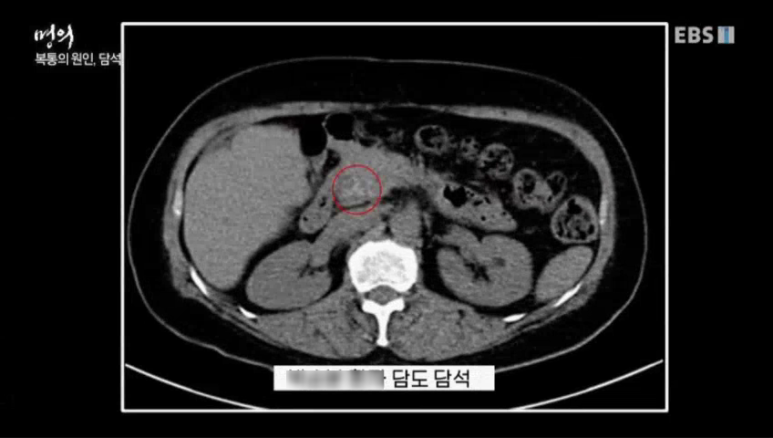

위 환자의 경우 담석이 담도를 막아 통증을 일으켰다.

환자의 CT 사진을 보면 전방담도에 담석이 확인된다. 이런 담석을 그대로 두면 염증이 심해져 합병증을 부를 수 있다. 환자는 담도 담석으로 간과 담낭까지 절제했다.